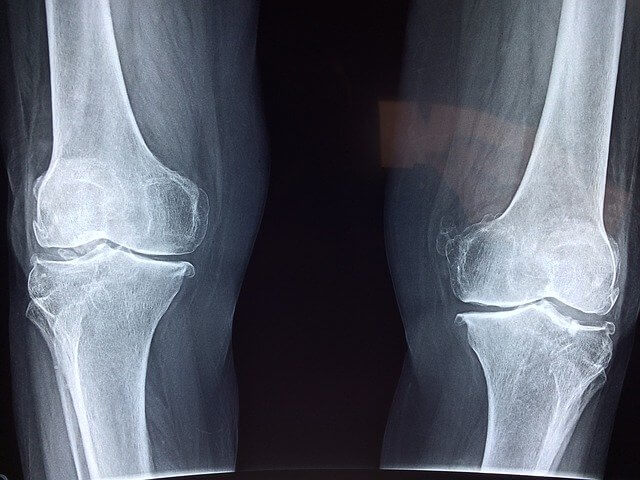

무릎에서 소리가 나는 이유는 몇 가지가 있습니다. 대표적인 것이 나이가 늘면서 노화 현상일 수 있습니다. 그 외에도 무릎 주변에 이상이 생겨서 일 수도 있습니다.

이와 연관된 질병으로는 <연골 연화증>, <퇴행성 관절염>, <추벽 증후군> 등이 있습니다. 이 세 가지가 대표적인 이유입니다. 그럼 하나씩 알아보겠습니다.

무릎에서 뚝뚝 소리나는 이유 중의 하나가 연골 연화증입니다. 그런데 연골 연화증은 뚝뚝 소리보다는 사가 사각 하는 소리가 난다고 합니다. 이름처럼 관절을 감싸고 있는 연골에 이상이 생기는 경우입니다. 연골을 관절을 감싸서 뼈로 전달되는 충격을 완화해 주는데 이 연골이 손상되면서 무릎을 꿇거나 쪼그려 앉았을 때 통증을 유발하게 됩니다.

퇴행성 관절염은 많은 사람들이 겪고 있는 증상입니다. 행성 변화로 인해 뼈와 인대가 손상되기 때문에 발생하는 데 딱딱하는 소리나 그르륵하고 뼈가 갈리는 듯한 소리가 나기도 합니다.